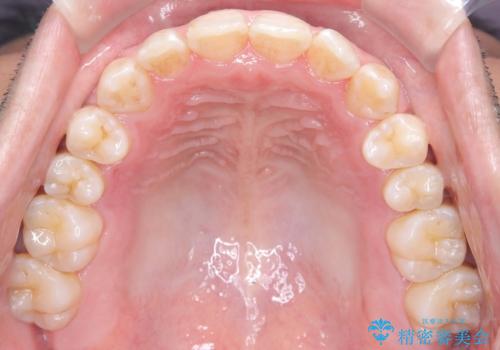

- 左上の八重歯を気にされて来院されました。精密な検査の結果、歯列全体を広げながら八重歯を奥へ移動させることで、美しい歯並びと機能的な咬み合わせが得られると診断。患者様のご希望に合わせ、透明で目立ちにくい**インビザライン(マウスピース矯正)**による治療計画を立案しました。抜歯を避け、歯を少しずつ遠心(奥)へ移動させることで、歯が並ぶスペースを確保し、叢生(歯のデコボコ)を改善します。

今回の矯正治療では、透明なマウスピース型の装置インビザラインを使用しました。この装置は目立ちにくく、取り外しが可能なため、食事や歯磨きも普段通りに行えます。遠心移動という方法で奥歯を後方に動かし、前歯を並べるためのスペースを確保。これにより、抜歯することなく、左上の八重歯を含む叢生を効果的に改善し、整った美しい歯並びと良好な咬み合わせを獲得していただけました。